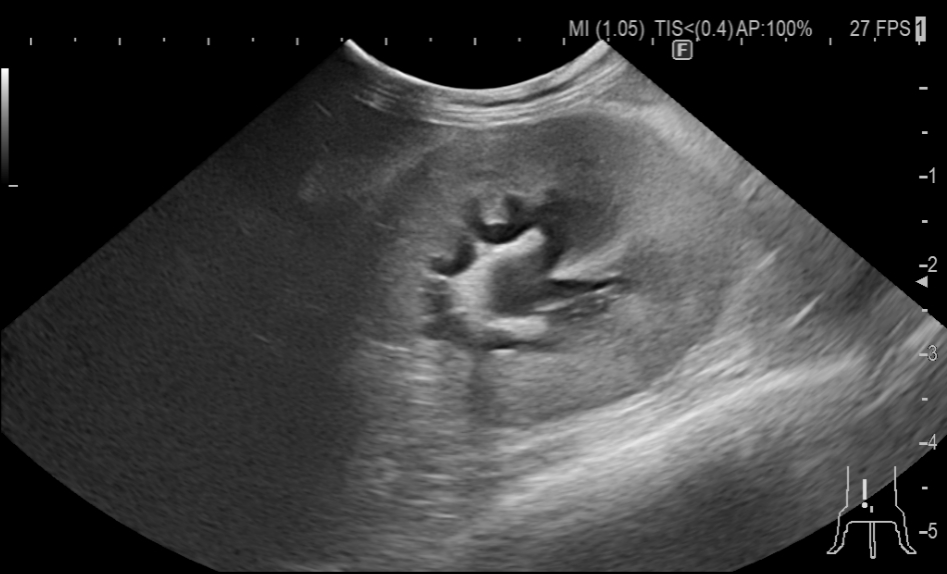

術前の超音波検査で腎盂の拡張はわずかではあるものの、腎盂圧の上昇の可能性が認められたためSUBシステム手術を検討することとしました。

腎臓にバイパスの管を入れたところです。